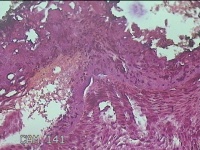

外阴赘生物

性别

女

年龄

33岁

临床诊断

外阴尖锐湿疣

一般病史

发现外阴尖锐湿疣4个月。

标本名称

大体所见

灰白暗红色不规则碎组织0.3x0.2x0.1cm一堆。

图1

良性病变,考虑湿疣。